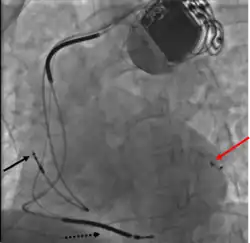

Pacemaker lead malposition in various locations has been described in the literature. Treatment varies, depending on the location of the pacer lead and symptoms.[55]